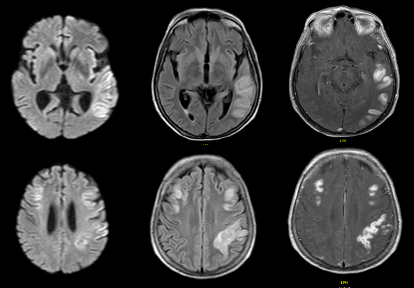

Se toma resonancia cerebral simple y con contraste con hallazgos de restricción a la difusión de predominio cortical temporoparietal bilateral, principalmente izquierdo, con extensión a insula izquierda, también representado como lesiones hiperintensas en FLAIR/T2 y con realce al contraste (Figura 1).

Figura 1